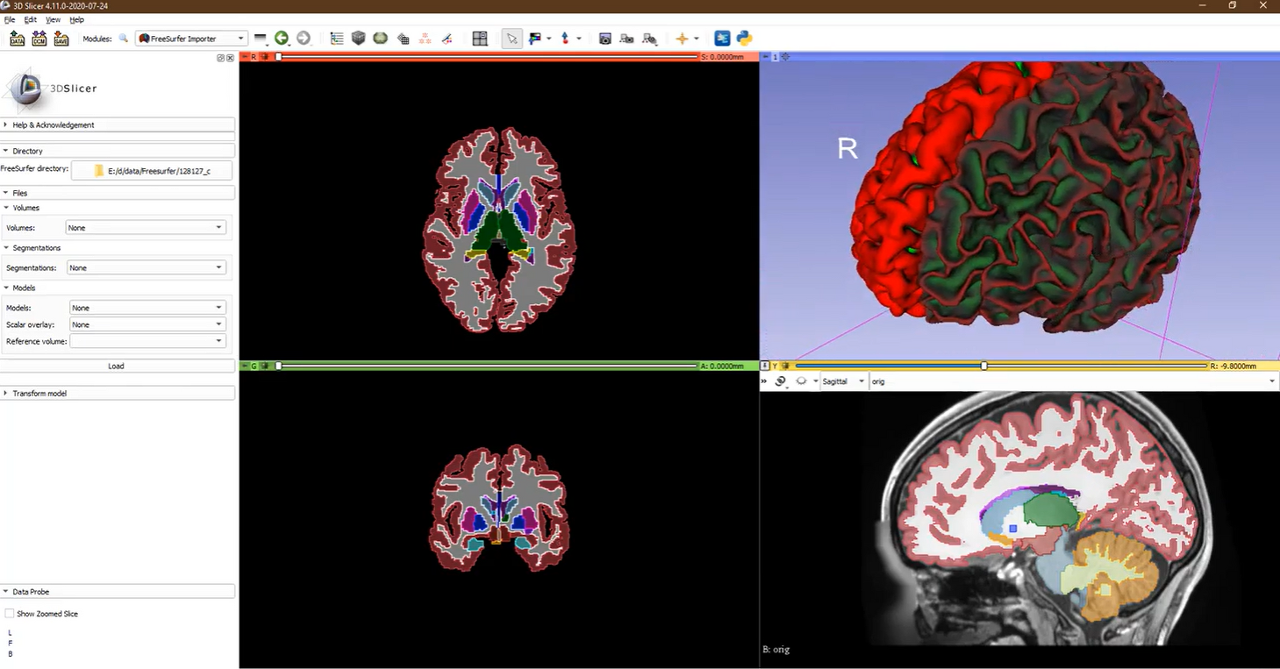

3D Slicer: 의료 영상 처리 및 분석을 위한 고품질 오픈소스 플랫폼입니다.